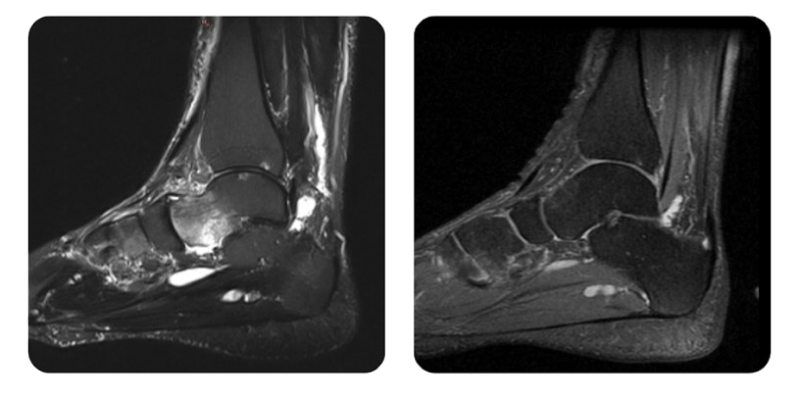

Prima

Dopo

M.Z., 51 anni - Edema del talo sinistro

Risultati: RMN della caviglia.

Diagnosi: Edema talar sinistro.

Il paziente ha riferito una riduzione significativa del dolore gia dalle prime sedute, seguita da un miglioramento della mobilita. Le indagini RMN hanno confermato la guarigione completa.